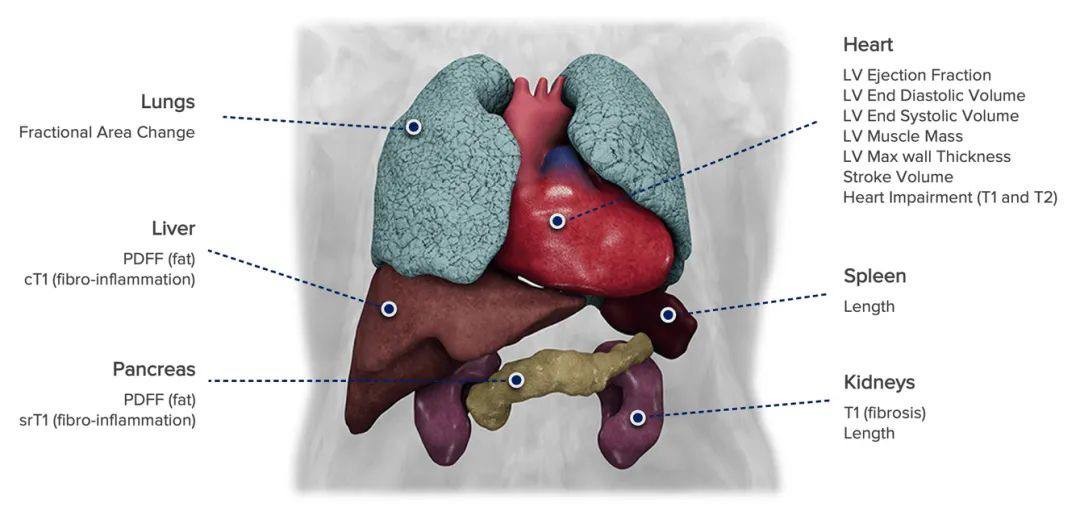

CoverScan|Perspectum

项目类型

器械质押区

起投金额

60000USDT

每日释放:0.85

释放周期:70 天

已购: 2500

剩余: 0